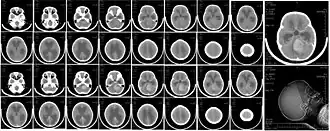

Scanner du cerveau d'une fillette de 6 ans atteinte d'un médulloblastome (tumeur cérébrale la plus fréquente chez les enfants de moins de 2 ans).

Le médulloblastome est un cancer qui apparaît (souvent avant la puberté) dans la moelle épinière à la base du cerveau, dans le cervelet ou la partie arrière du cerveau ; c'est le plus courant des cancers du cerveau de l'enfant[4].